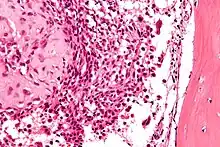

Micrograph of a chondroblastoma. H&E stain.

Chondroid differentiation is a common feature of chondroblastoma.[1][4][6] A typical histological appearance consists of a combination of oval mononuclear and multi-nucleated osteoclast-type giant cells.[1][3][4] However this is not a prerequisite for diagnosis, as cells with epithelioid characteristics have been observed in lesions of the skull and facial bones.[4] A "chicken-wire" appearance is characteristic of chondroblastoma cells and is the result of dystrophic calcification that may surround individual cells.[1][5] Although, calcification may not be present and is not a prerequisite for diagnosis.[1][3][4] Mitotic figures can be observed in chondroblastoma tissue but are not considered atypical in nature, and therefore, should not be viewed as a sign of a more serious pathology.[1][4] There is no correlation between mitotic activity and location of the lesion.[4] Furthermore, the presence of atypical cells is rare and is not associated with malignant chondroblastoma.[1][6] There are no discernible histological differences observed when comparing the aggressive form of chondroblastoma that can cause recurrence or metastases with its less aggressive, benign, counterpart.